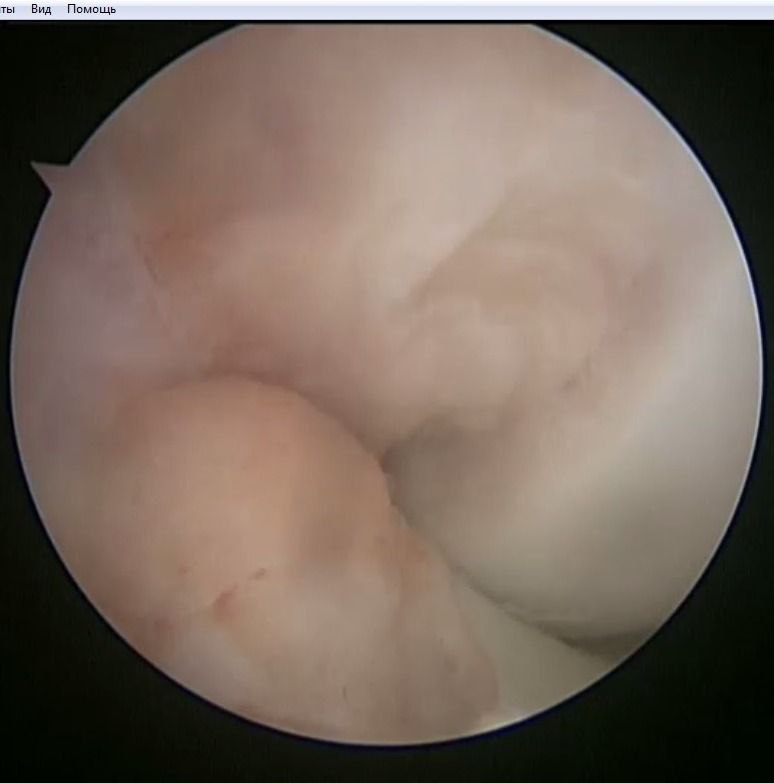

Наложения артроскопического шва заднего рога медиального мениска

По итогам исследования и определения диагноза пациенту был предложен и реализован план лечения: предоперационная реабилитация и проведение операции по поводу наложения артроскопического шва заднего рога медиального мениска, а также проведена пластика передней крестообразной связки сухожилием полусухожильной и тонкой мышц правого коленного сустава.